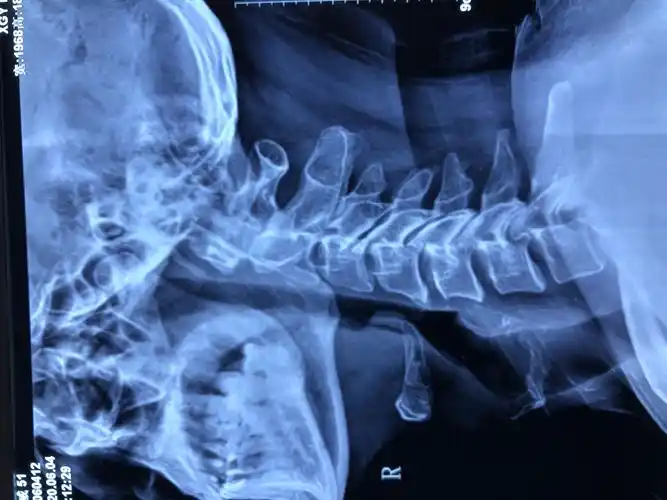

医生说这个就是正常的颈椎侧位dr片了,叫我比较.

颈部x线片(侧位片)

颈椎侧位片

颈椎侧位片提示轻度增生,生理曲度稍偏直,无项韧带钙化,椎体滑脱等